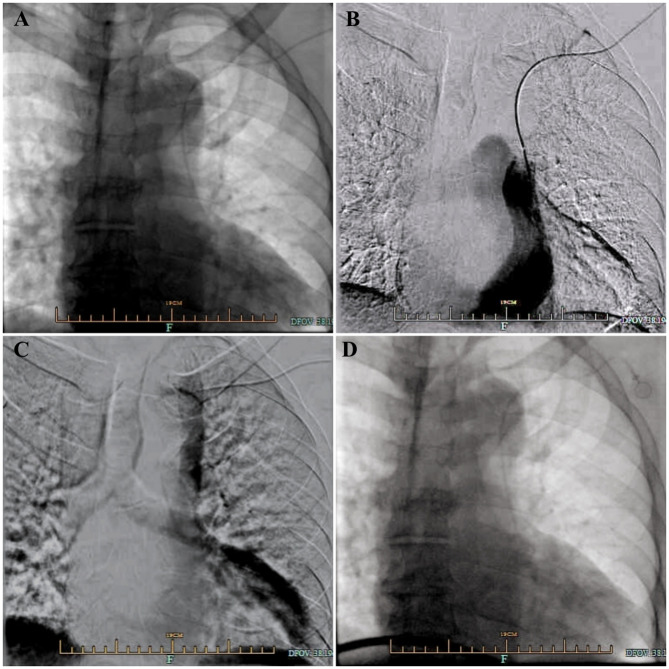

Venous Port implantation in persistent left superior vena cava with azygos vein variation: a case report and literature review.